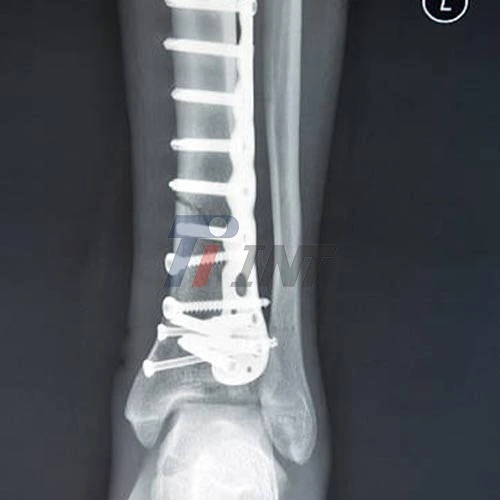

Before focusing on post-operative care, it’s essential to understand the role of a titanium plate in your leg. Titanium plates are biocompatible, meaning they are easily accepted by the body. These plates are commonly used to stabilize fractured bones or aid in realigning bones during the healing process. Their strength and durability make them ideal for supporting bone repair and ensuring proper recovery, minimizing complications and promoting long-term healing.

Regular check-ups with your orthopedic surgeon are essential to monitor healing progress and address any concerns. These appointments may include X-rays to assess bone healing and the position of the titanium plate.